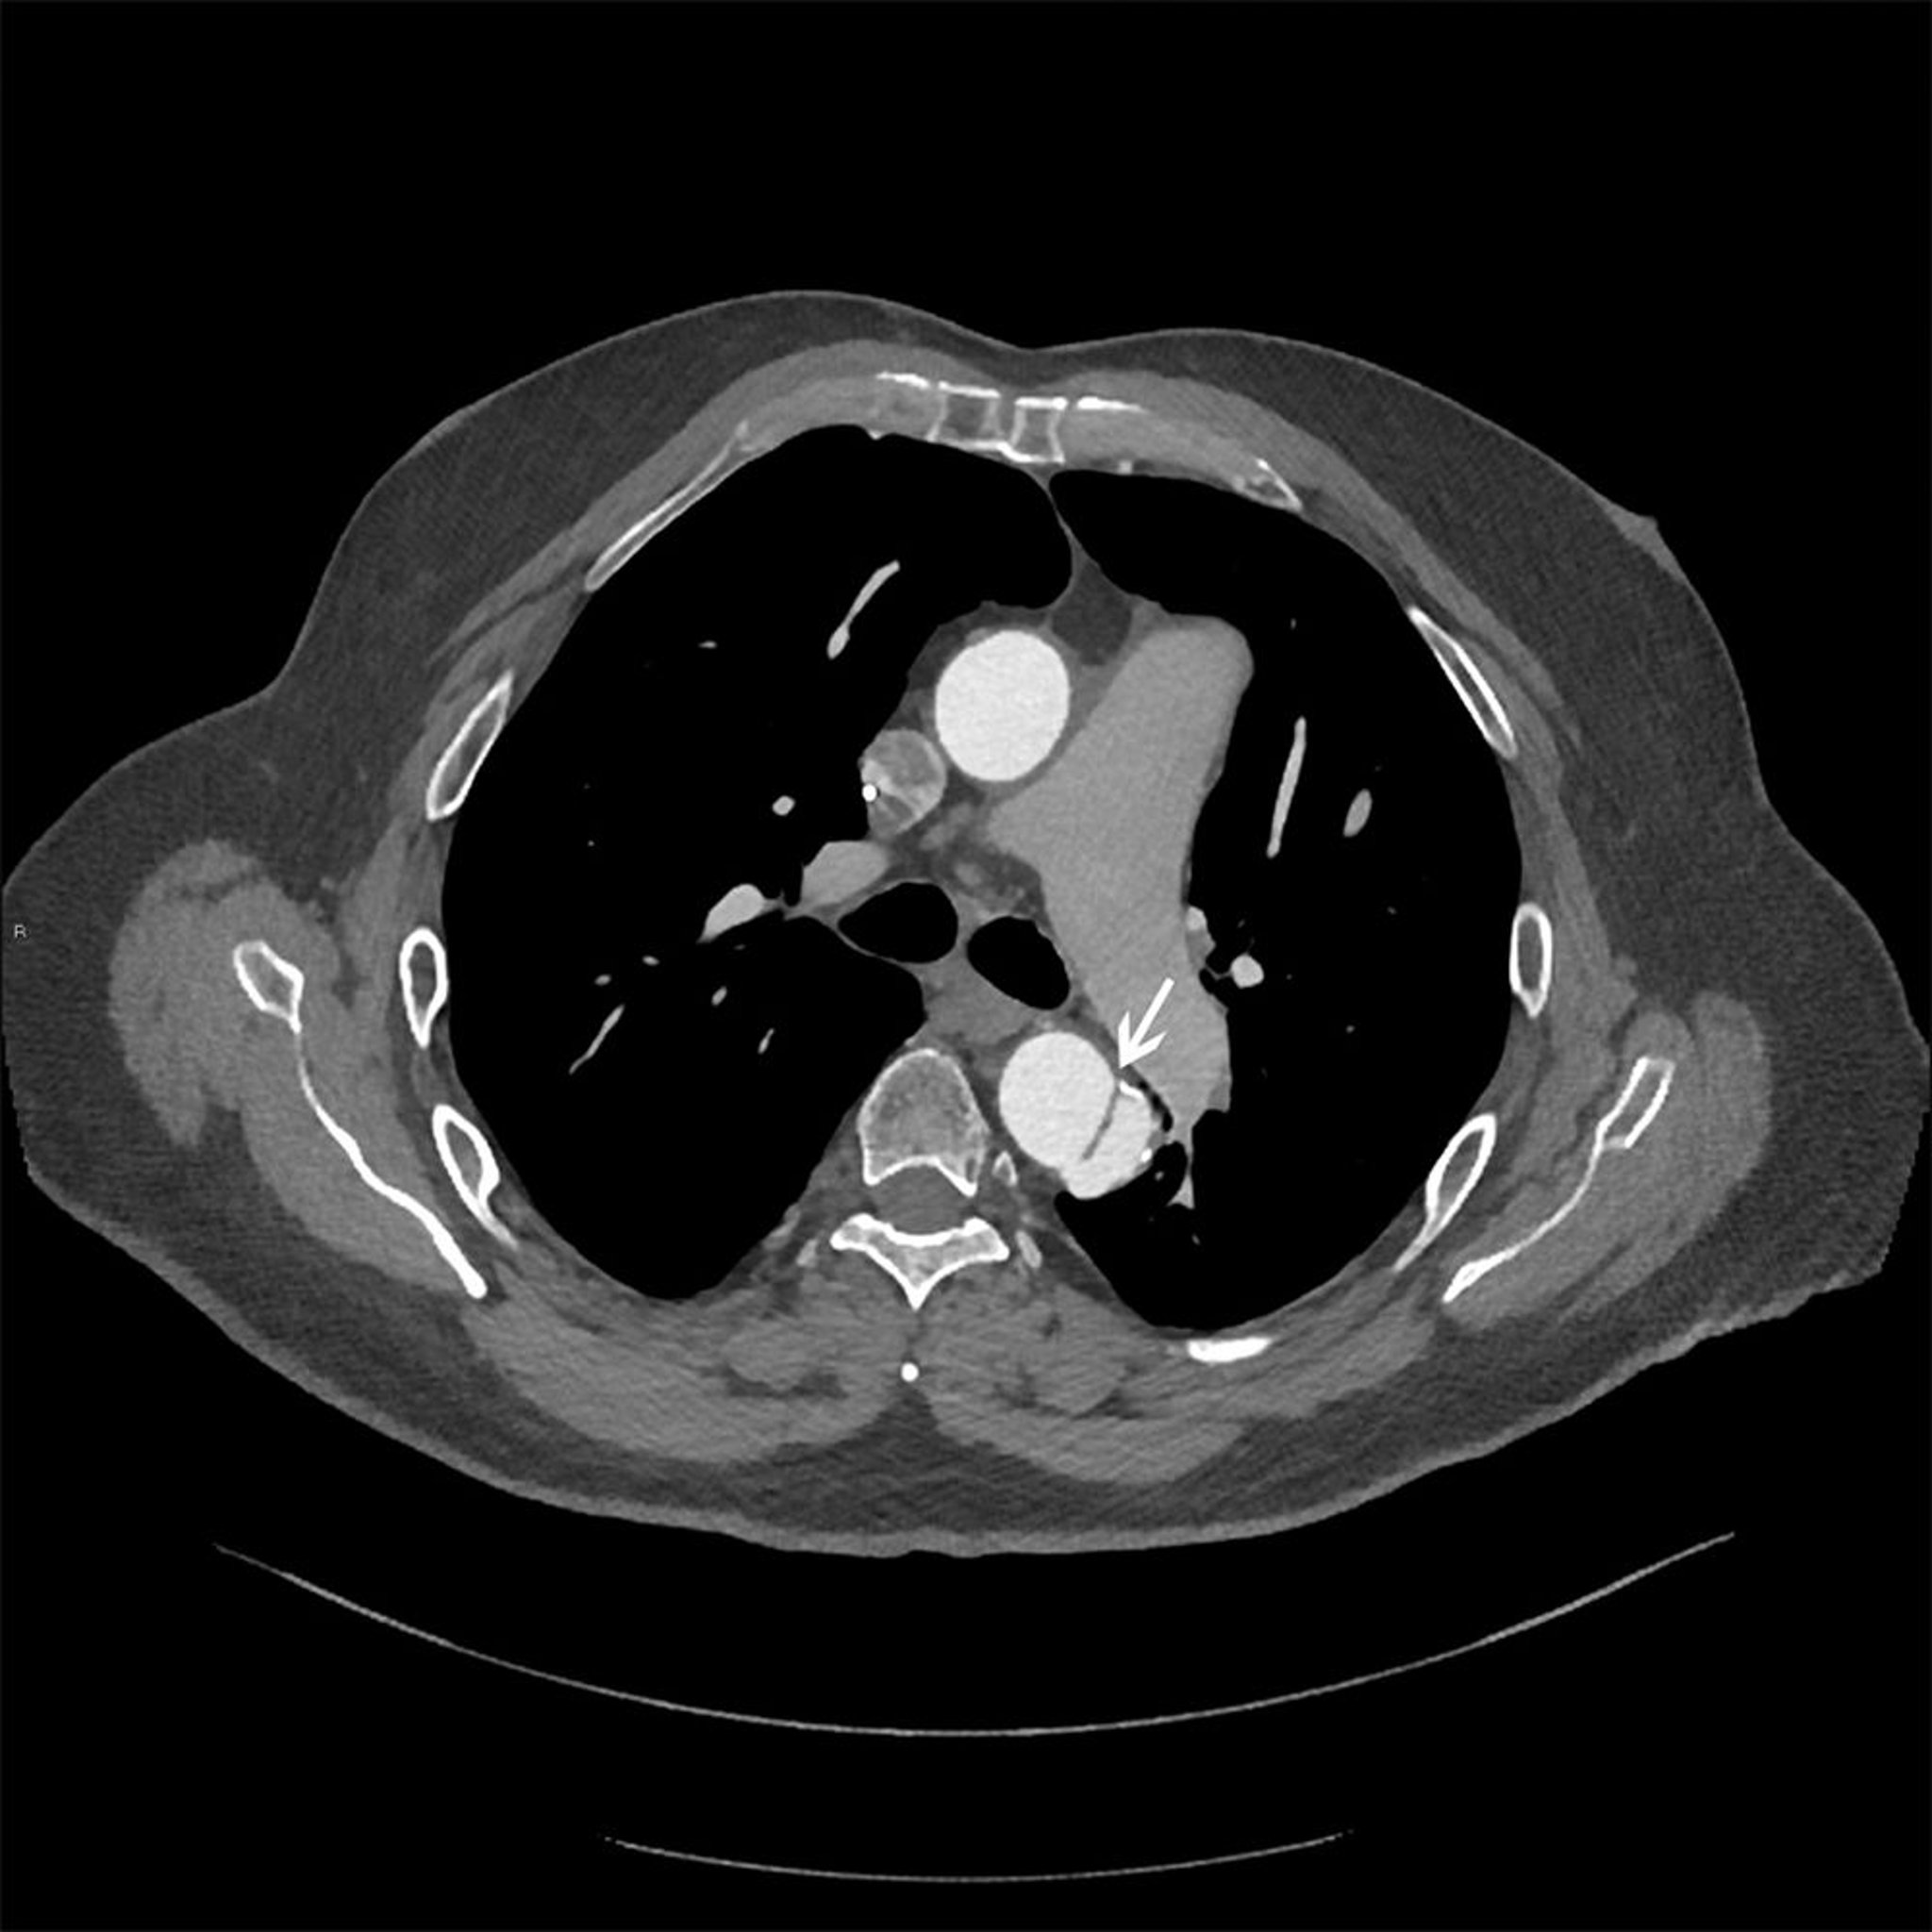

Расслоение грудной аорты в грудном отделе (Стенфорд, тип В)

Осевое изображение расслоенного лоскута (белая стрелка) в нисходящей грудной аорте.